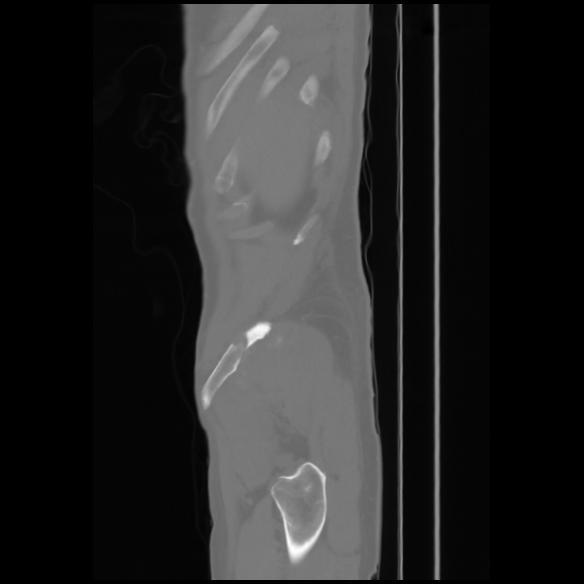

7 CUERPO,CE,Sagittal,3.000,CUERPO,Sagittal,